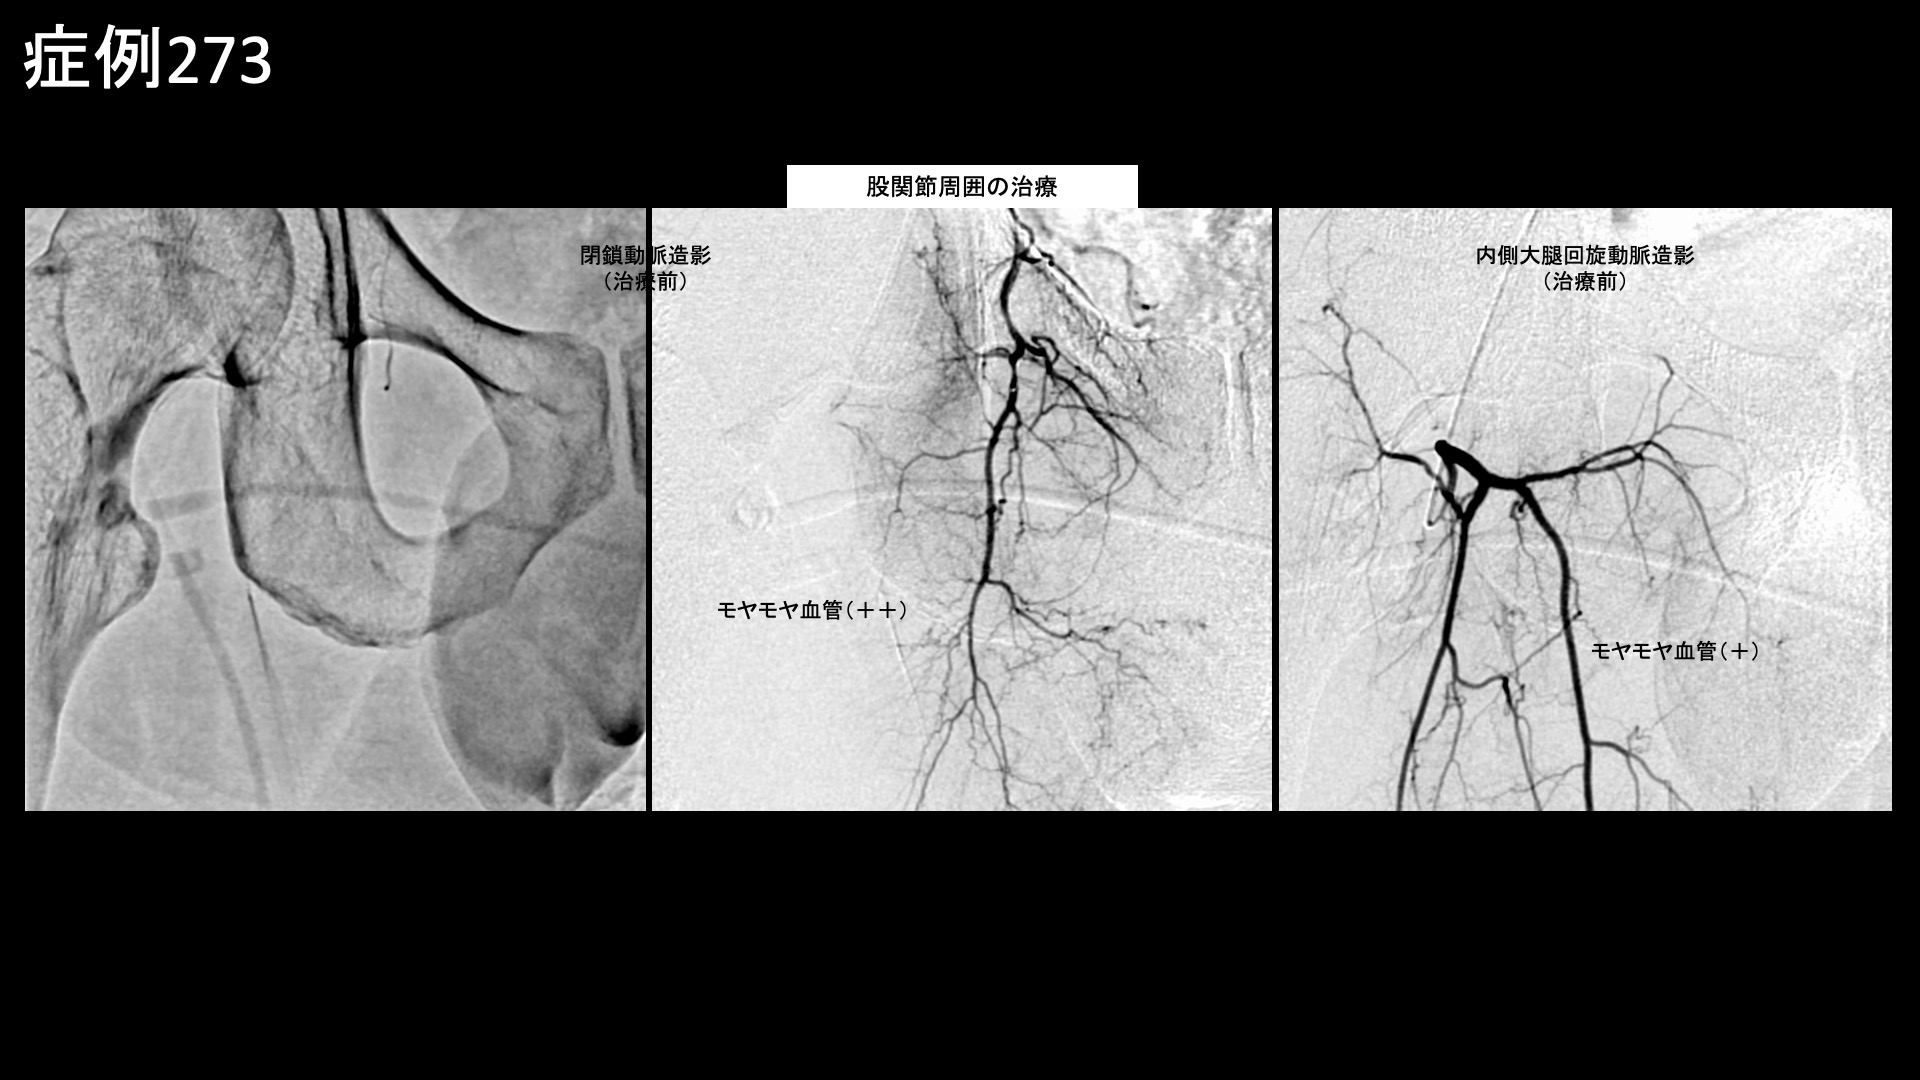

足:アキレス腱炎、足底筋膜炎、踵骨棘など 【30代:男性】マラソンランナーに生じた大腿裏付け根の痛み、ハムストリングス付着部炎に対するモヤモヤ血管治療(ハムストリングス付着部炎、仙腸関節障害) 2026.03.24 鴨井院長による動画解説 受診までの経過 マラソンにも参加するなどランニングを趣味としている方です。週に5-6回、14km/日程度走るのを日課としていましたが、9ヶ月前から右脚付け根の後ろ側、ハムストリングス付着部が痛むようになりました。その後も5ヶ月くらいはだましだましランニングを続けていましたが、症状が悪化してきたため走るのをやめて鍼灸治療に通いました。しかしながら、あまり改善がみられませんでした。その内に、ぎっくり腰を何回か起こし、腰痛も併発するようになりました。できればランニングは続けながら治したいという希望で、当院を受診されました。 診察時の所見 腰の動きを確認すると、前屈で中等度以上の制限があり、腰部や右ハムストリングス付着部に疼痛が誘発されました。後上腸骨棘近傍に圧痛を認めました。右ハムストリングス付着部において圧痛を認めたほか、負荷テストでも陽性でした。股関節は問題ありませんでした。レントゲンでは仙腸関節の骨硬化像や、開大傾向が認められました。ハムストリングス付着部である坐骨の骨表層不整像も認められました。その他の診察所見を含めて総合的に判断し、右ハムストリングス付着部炎および仙腸関節障害と診断しました。治療適応と判断し、モヤモヤ血管(病的新生血管)に対する運動器カテーテル治療(微細動脈塞栓術)を受けていただきました。 治療の所見 ハムストリングス付着部に重要な下殿動脈の分枝を治療した後、腰痛に対する腸腰動脈等を治療しました。ハムストリングス付着部炎においては、股関節周囲の血管も重要です。閉鎖動脈や内側大腿回旋動脈の血管造影では、モヤモヤ血管が濃染像として描出されました。治療後は画像上速やかに消失しました。それぞれで、再現痛も明瞭に確認されました。その他複数箇所の治療を行い終了しました。 *再現痛とは、薬液投与時に普段の痛みが一定程度再現される現象です。責任血管の同定のための参考とします。特に腰臀部領域ではモヤモヤ血管が描出されにくいため、再現痛の確認が重要です。 治療後の経過 治療翌日には炎症感がおさまり、2日後に再燃したように感じましたが、そこからどんどんと良くなってきました。治療後2週間、実は起床時の症状が最も悪かったのですが、それがだいぶ気にならなくなりました。痛みが良くなったためか、突っ張り感が気になりました。診察では、後上腸骨棘近傍の圧痛は消失していました。その翌日に、ハムストリングス付着部の違和感が消失しました。治療後3週間くらいで10kmほどランニングをしてみたところ、再び違和感が生じ、しばらく続きましたが、1週間くらいで気にならなくなりました。治療後1ヶ月半、前述内容の申告からランニング再開には時期尚早と判断し、1ヶ月ほど控えていただくこととしました。治療後2ヶ月半、日常生活ではほとんど痛みを感じることが無くなりました。徐々に運動を再開することとしました。走った後に炎症を感じたものの、元の状態からすると8-9割方改善しているということでした。治療後3ヶ月、16km/日のランニングを行うことができ、翌日に引きずるような症状もありませんでした。順調に改善していました。腰痛の訴えも無くなっていました。引き続き、慎重にフォローアップしていく予定です。 ハムストリングス付着部炎はモヤモヤ血管治療の適応疾患の一つであり、痛みは良く治まりますが、実際には同部位の組織損傷があるため、運動再開のリスクは個人差がかなり大きいです。重症になるほど、運動の再開は慎重にならなければなりません。特に、日常生活でも痛みが生じる内は負荷の大きなランニングは控える必要があります。痛みをこらえて、だましだまし走り続けると状況が悪化してしまいます。安静にするべき時は安静を守っていただき、しっかり治してからまた楽しんでいただきたいと思います。 ハムストリング付着部炎の詳細はこちら 【40代:女性】2年間悩まされた、交通事故後に絶えまなく続く首の痛み(むち打ち症;頸椎捻挫後遺症)に対するモヤモヤ血管治療(むち打ち症、頸椎捻挫後遺症、交通事故後遺症) 前の記事 【70代:女性】それほど目立たない発疹だったのにこんなに痛くなるなんて・・下腹部、脇腹に生じた発症1ヶ月半の帯状疱疹後神経痛 次の記事